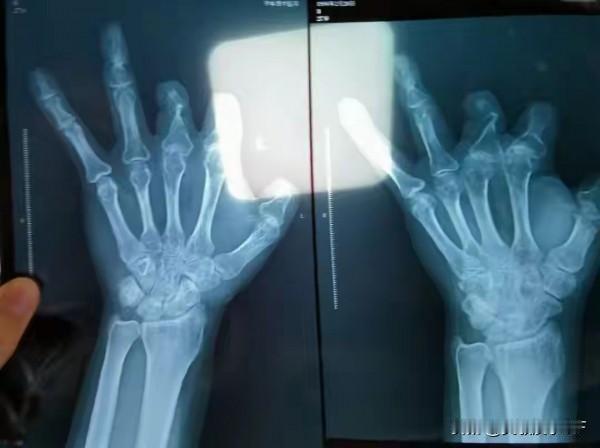

2018年的郑州工地,电锯切断王海森左手拇指的瞬间,他以为人生的苦难不过是皮肉之痛。紧急送医后,郑大一附院急诊外科副主任医师王福建的出现,让他看到了希望,这位顶着“全国知名专家”光环的医生,承诺用进口微血管吻合装置确保手术成功。当术后清单递到面前,王海森虽心疼那笔足以掏空家底的费用,但在“救命要紧”的执念下,还是咬牙签字,术后第二天便因无力承担后续费用匆匆出院。出院后的三年里,王海森的手指始终未能完全恢复灵活,但他从未怀疑过那场手术。直到2021年12月,同乡工友的一句提醒:“那器械根本不适合手指,你没拍片子看看?”如惊雷般唤醒了他。带着忐忑与不安,他回到老家医院拍片,当医生告知“片子里什么都没有”时,王海森如遭雷击。 他疯了似的翻出三年前的费用清单,对比着空白的X光片,一股被欺骗的愤怒与无助涌上心头。联系郑大一附院时,他遭遇的却是推诿敷衍,王福建仅通过助理给出“血管不通被切除”的苍白解释。但王海森没有放弃,他四处打听,竟发现还有更多受害者:中牟县的彭先生四根手指离断,被收取10.08万元的6个吻合装置费用,术后X光片同样空空如也;甚至有1岁婴儿在手指手术中被违规计费。 真相的碎片逐渐拼凑,2021年12月底,王海森攥着费用清单与X光片,毅然走进了公安局。这张看似普通的影像资料,成为了揭开惊天黑幕的关键证据。 随着王海森的报案,更多受害者陆续浮出水面,94名被王福建诈骗的患者相继举证,涉案金额高达205万余元。2025年12月,郑州市中级人民法院作出终审判决,王福建因诈骗罪、非国家工作人员受贿罪,被判处有期徒刑12年,罚金40万元,违法所得全部追缴。这场由木工王海森执着追凶三年揭开的医疗黑幕,不仅让贪婪的医生受到了法律的严惩,更推动了医疗行业对高价耗材的监管改革,而王海森那张空空如也的X光片,也成为了医疗反腐史上最沉重的见证。